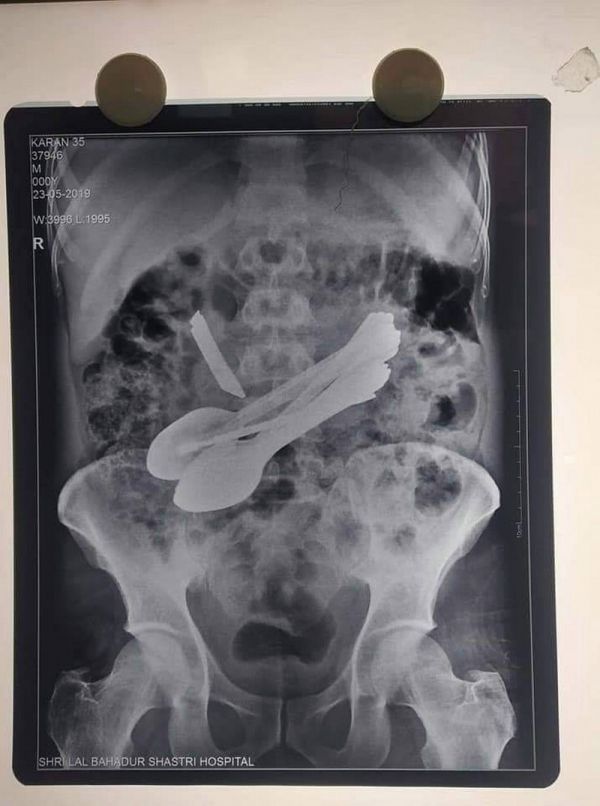

К индийским медикам обратился мужчина с болями в животе, он был доставлен в правительственный медицинский колледж Лал Бахадур Шастри в районе Манди, Индия, где врачи сделали рентген и четко обнаружили столовые приборы внутри кишечника пациента и решили оперировать. Во время процедуры врачи удалили семь маленьких стальных ложечек, две зубные щетки, две маленькие отвертки, маленький нож и стержень.

Операцию провела объединенная команда врачей. Медики предположили, что у пациента было редкое расстройство, называемое Пика (Pica), когда люди жаждут есть необычные предметы.